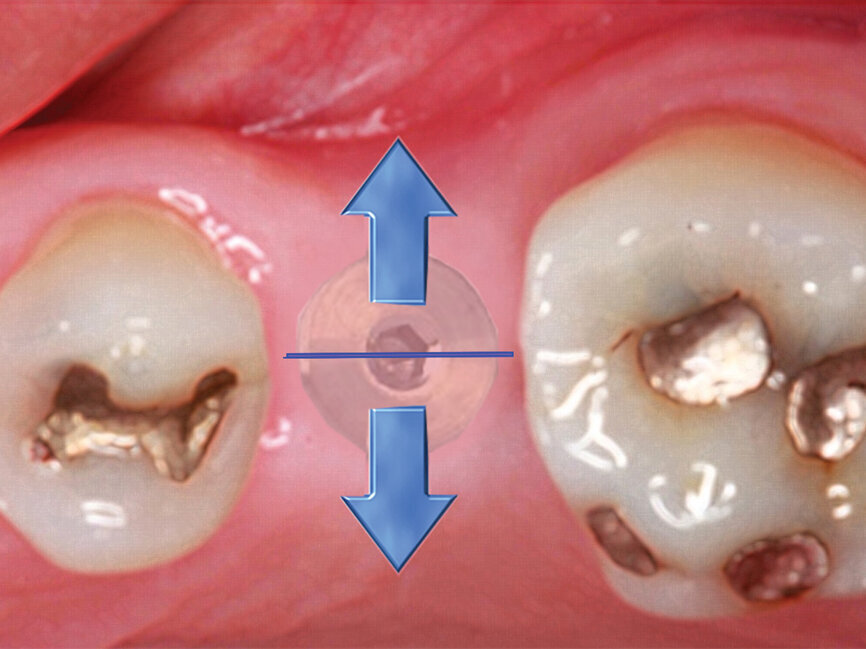

Figs. 4a: Implant to be uncovered (4a) presents with two options depending on width of attached gingiva available. Wide band of attached gingiva will remain after removal of tissue over cover screw, and the diode is utilized in a spiral pattern starting at center until fully exposed (4b). With the narrow band of attached gingiva present, an elliptical cut is made with the diode and tissue is pushed buccally and lingually to preserve the attached gingiva (4c). (Photo provided by Dr. Gregori M. Kurtzman)

The width of attached gingiva remaining will dictate the best method for implant uncovery (Fig. 4a). When a wide band of attached gingiva is present and a sufficient amount (3 mm or greater) will be present after uncovery on both the buccal and lingual, then the diode laser is activated and inserted at the center of the site and worked in a spiral pattern outward until the entire cover screw is exposed (Fig. 4b).